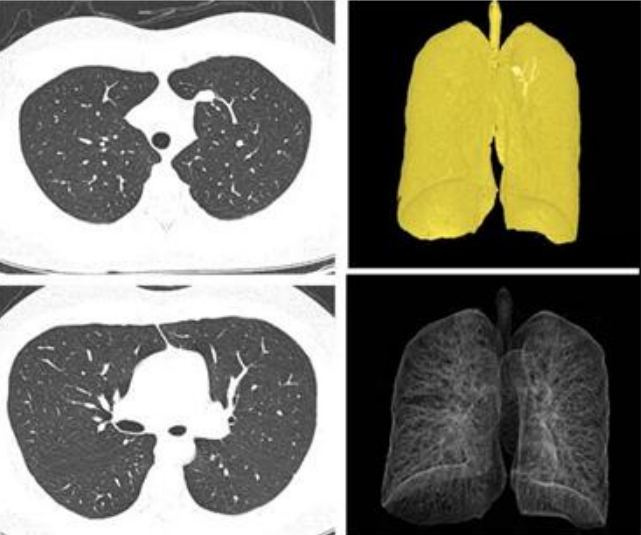

例如临床肺癌患者首次就医常因有明显的症状或传统胸部平片检查发现病灶,因此确诊时80%以上是中晚期肺癌,往往失去了根治性手术治疗的机会,总体5年生存率不足15%,临床疗效差,生存期短。Revolution CT在低剂量肺癌筛查扫描(LDCT),借助低剂量螺旋CT能检出直径小于1.0cm的小肺癌,在高危人群中进行的筛查中,早期肺癌的检出率可达80%,筛查的患者中80%~90%可通过微创手术切除治疗,无须进一步放疗和化疗。GE 公司推出的全新的Revolution CT ,具有16cm 宽体探测器及ASiR-V重建技术,胸部扫描覆盖范围大,扫描速度快,辐射剂量低,实现了早期肺癌低剂量精准成像。

GE病人列表怎么删除​【院之重器】GE Revolution 256排超高端CT:让诊断更快,更精准!_https://www.jmylbn.com_新闻资讯_第6张

Revolution CT常规低剂量扫描模式,可清晰显示病灶及其周围肺实质特征